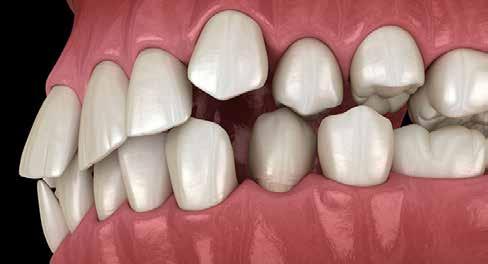

A fogászati kezelések során manapság már nem kizárólag az esztétikai megjelenés helyreállítására törekszünk. Sokszor a kedvezőtlen esztétikai megjelenés hátterében álló okok következményes módon a fogazat funkcionális működését is károsítják, így a kezelések során ezeknek a helyreállításával is foglalkoznunk kell. A különböző funkcionális és esztétikai diszkrepanciák kezelésére számtalan módszer létezik, ám ezen fogászati beavatkozások mindegyikében közös, hogy a kivitelezésük során nagyon szoros együttműködésre van szükség a kezelést végző fogorvos és a munkáját segítő fogtechnikus között. Az alábbi esetbemutatás során egy fiatal hölgypáciens fogazatának héjak alkalmazásával történő esztétikai és funkcionális rehabilitációját szeretnénk ismertetni.

A 19 éves hölgypáciens azzal a kéréssel jelentkezett a rendelőnkbe, hogy szebb fogakat szeretne. Az első konzultáció alkalmával megkérdeztük, hogy mi zavarja leginkább a fogazatának jelenlegi megjelenésében, valamint azt is megbeszéltük vele, hogy milyen végeredmény elérése esetén lenne maradéktalanul elégedett. Ebben az esetben a kezelési célokat az alábbiakban határoztuk meg:

A páciens fogazata esztétikai megjelenésének és funkcionális működésének a lehető legtöbb, saját foganyag megtartása mellett történő helyreállítása (1. és 3. ábra).

A lehető legideálisabb esztétikai végeredmény elérése érdekében néhány esetben a fogak alakjának módosítá -